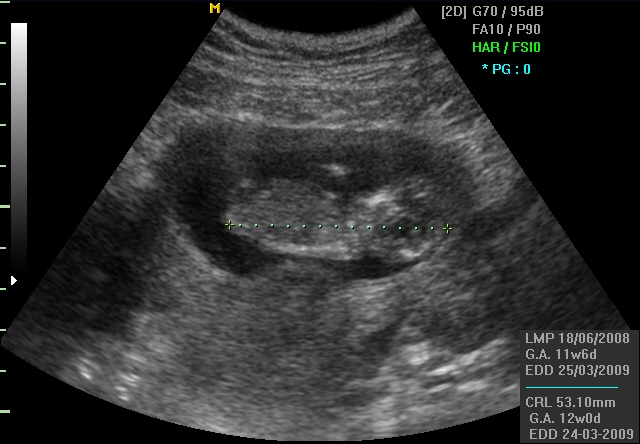

CRL (Crown-rump length) претставува должината на плодот која се мери во периодот помеѓу 7. и 13. гестациска недела. Оваа мерка во раната бременост дава релативно добра прогноза за гестациската старост на плодот и ВТП.